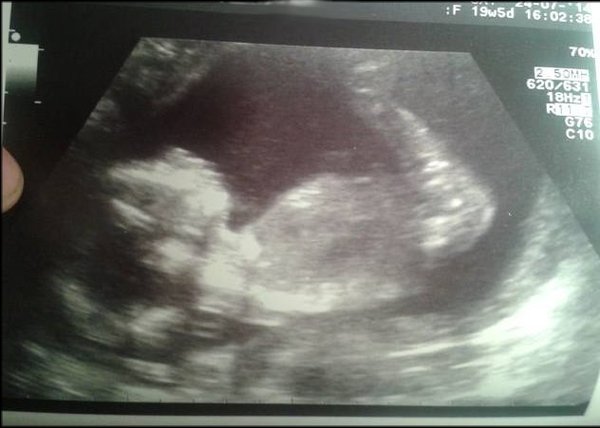

In more positive news, 20 week scantoday went well, aside from a very uncooperative baby who insisted on leaving its head in my pelvis/under my right hip! got a pic or 2 but not great quality, so heres the best! Everything healthy looking, we even glimpsed some toes in there ;) DH and I are leaning towards it being a girl, as he saw no testicles (I was more worried about not being able to check brain/face!) and hes just got this feeling :) I'll take that!

19+5